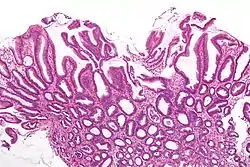

| Micrograph of a reactive gastropathy. H&E stain. | |

- Foveolar hyperplasia (black arrow), as a tortuosity in the "neck" region of the gastric glands.

- Scant or minimal inflammatory cells (white arrow), i.e. lack of large numbers of neutrophils and plasma cells..

- Smooth muscle hyperplasia in the lamina propria (in black oval).

The diagnosis is by examination of tissue, e.g. a stomach biopsy.

Low mag.

Low mag. High mag.